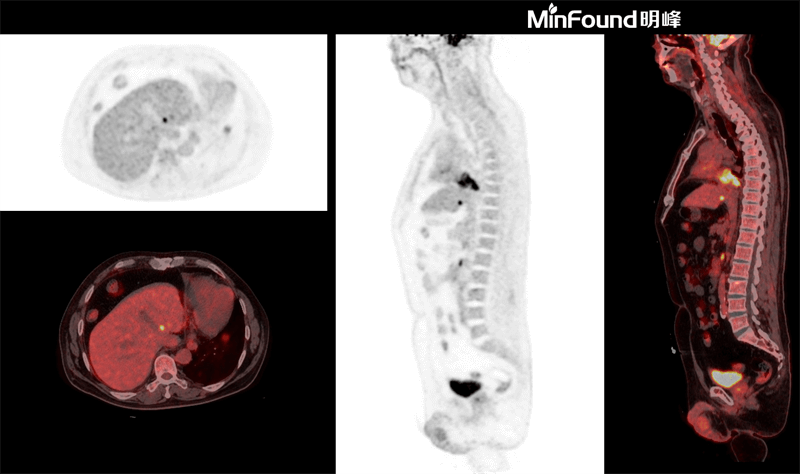

ScintCare PET/CT 730T employs a 4th-generation PET detector where lutetium-yttrium oxyorthosilicate (LYSO) crystals are individually coupled to SiPM detectors without the optical conductor (1: 1 coupling and 100% coverage). The digital SiPM detector considerably minimizes photon loss, resulting in improved time resolution (380 ps), system sensitivity (23.5 cps / kBq), and image uniformity, ultimately resulting in high-resolution images under well-curated radiation dose control.

ScintCare PET/CT 730T axial FOV reaches 40.3 cm width, enabling the whole-organ scan just by one-bed position and the whole-body scan by two-bed positions in about 3 minutes time. The ultra-fast data acquisition greatly supports the large patient throughput.

臨床畫廊